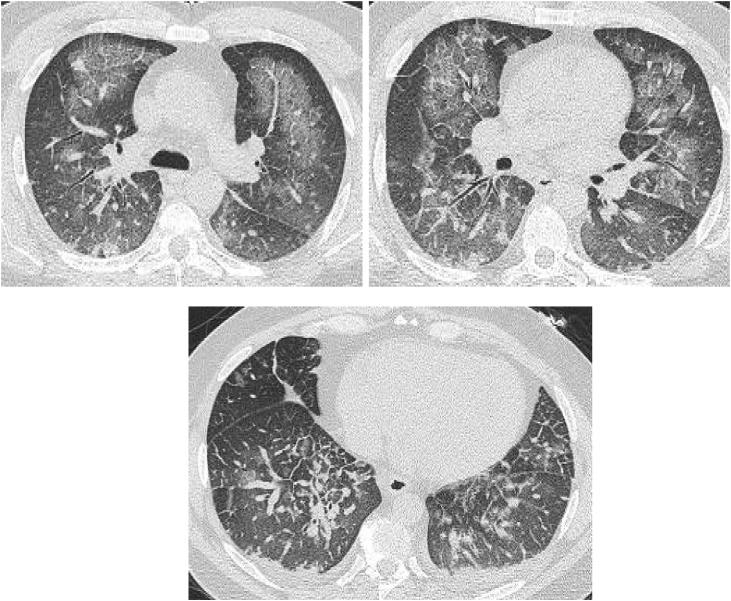

Pulmonary edema is a common clinical entity caused by the extravascular movement of fluid into the pulmonary interstitium and alveoli. The four physiologic categories of edema include hydrostatic pressure edema, permeability edema with and without diffuse alveolar damage (DAD), and mixed edema where there is both an increase in hydrostatic pressure and membrane permeability. As radiographic manifestations and etiologies are varied, an appreciation for both the common and uncommon manifestations and causes of pulmonary edema is essential for accurate diagnosis.

肺水肿是一种常见的临床病症,由液体向肺间质和肺泡的血管外移动所致。水肿的四种生理类型包括静水压性水肿、伴有或不伴有弥漫性肺泡损伤(DAD)的通透性水肿,以及静水压和膜通透性均增加的混合性水肿。由于影像学表现和病因各不相同,了解肺水肿的常见和不常见表现及病因对于准确诊断至关重要。